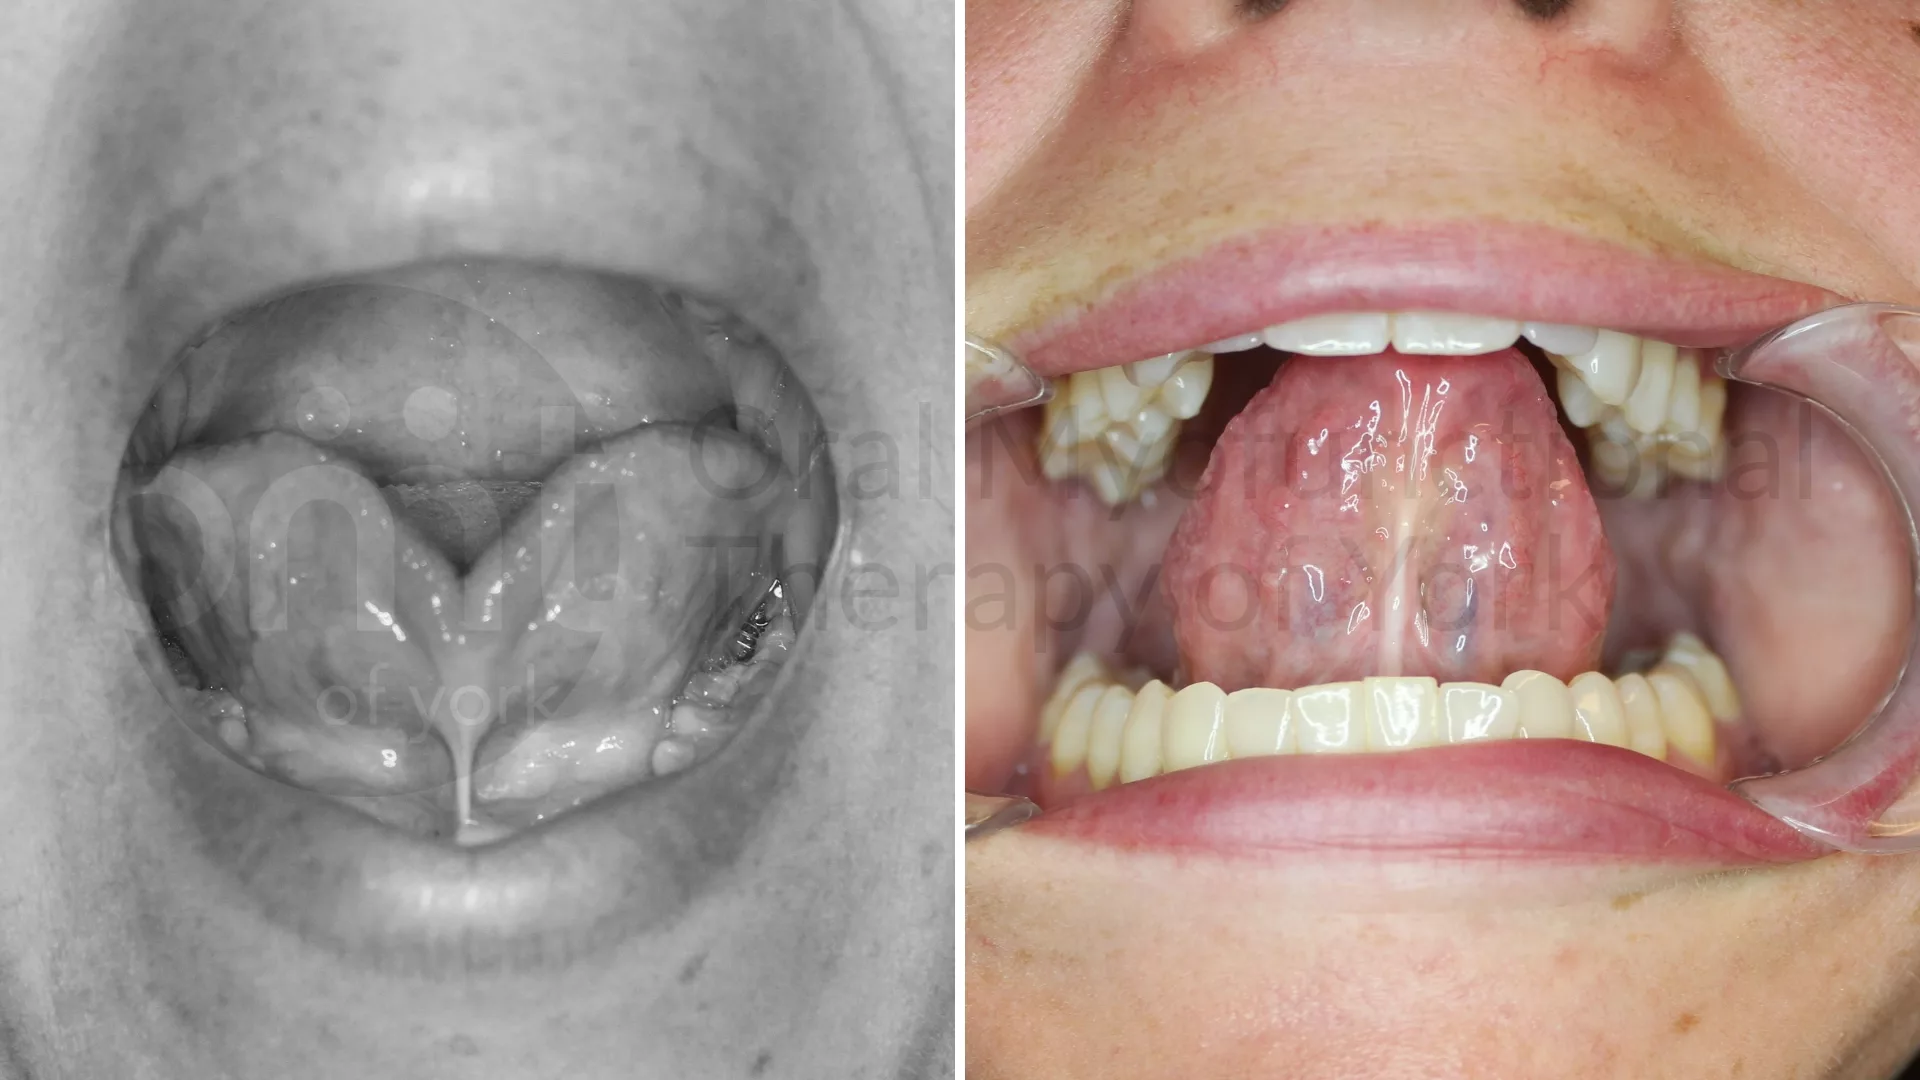

Improved oral rest posture and reduction of migraines after a tongue tie release and 4 months of OMT.

Improved oral rest posture and reduction of migraines after a tongue tie release and 4 months of OMT